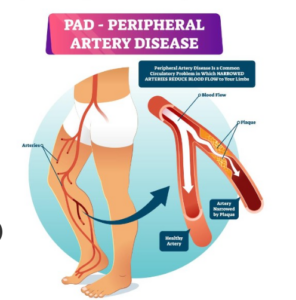

The Lifeline: Circulation and Peripheral Artery Disease (PAD)

While arthritis affects the “hardware” of the foot, circulation issues involve the “plumbing.” As we age our arteries can narrow due to a buildup of plaque – a condition known as Peripheral Artery Disease (PAD).

In Southwest Florida, where the climate is warm, many seniors assume their feet are healthy because they aren’t “cold.” But circulation is about more than temperature; it’s about the delivery of oxygen and nutrients. When blood flow is restricted, the skin on the feet may become thin and shiny, toenail growth slows down, and hair on the lower legs may disappear.

The danger here is twofold. First, PAD causes claudication – cramping or leg pain that occurs during walking and disappears with rest. Second, and more critically, poor circulation means poor healing. A small blister from a new pair of shoes or a minor “Naples pier splinter” can quickly escalate into a non-healing ulcer or infection because the body simply cannot deliver the “repair crew” of blood cells into the site.